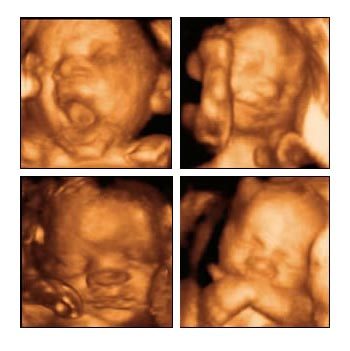

La ecografía en 4D, como ya explicamos hace tiempo, es aquella que nos permite conseguir una imagen tridimiensional y en movimiento del bebé.

El momento recomendado para realizarse este tipo de ecografías es entre las semanas 23 y 34, que es cuando factores como la cantidad de líquido amniótico, el tamaño del bebé, el espacio disponible o su colocación hacen que sea más fácil conseguir buenas imágenes del bebé.

Una vez realizada te entregan las fotos y el vídeo en DVD del bebé. Opcionalmente pueden quedar almacenadas online durante un año para compartirlo con quien queramos.